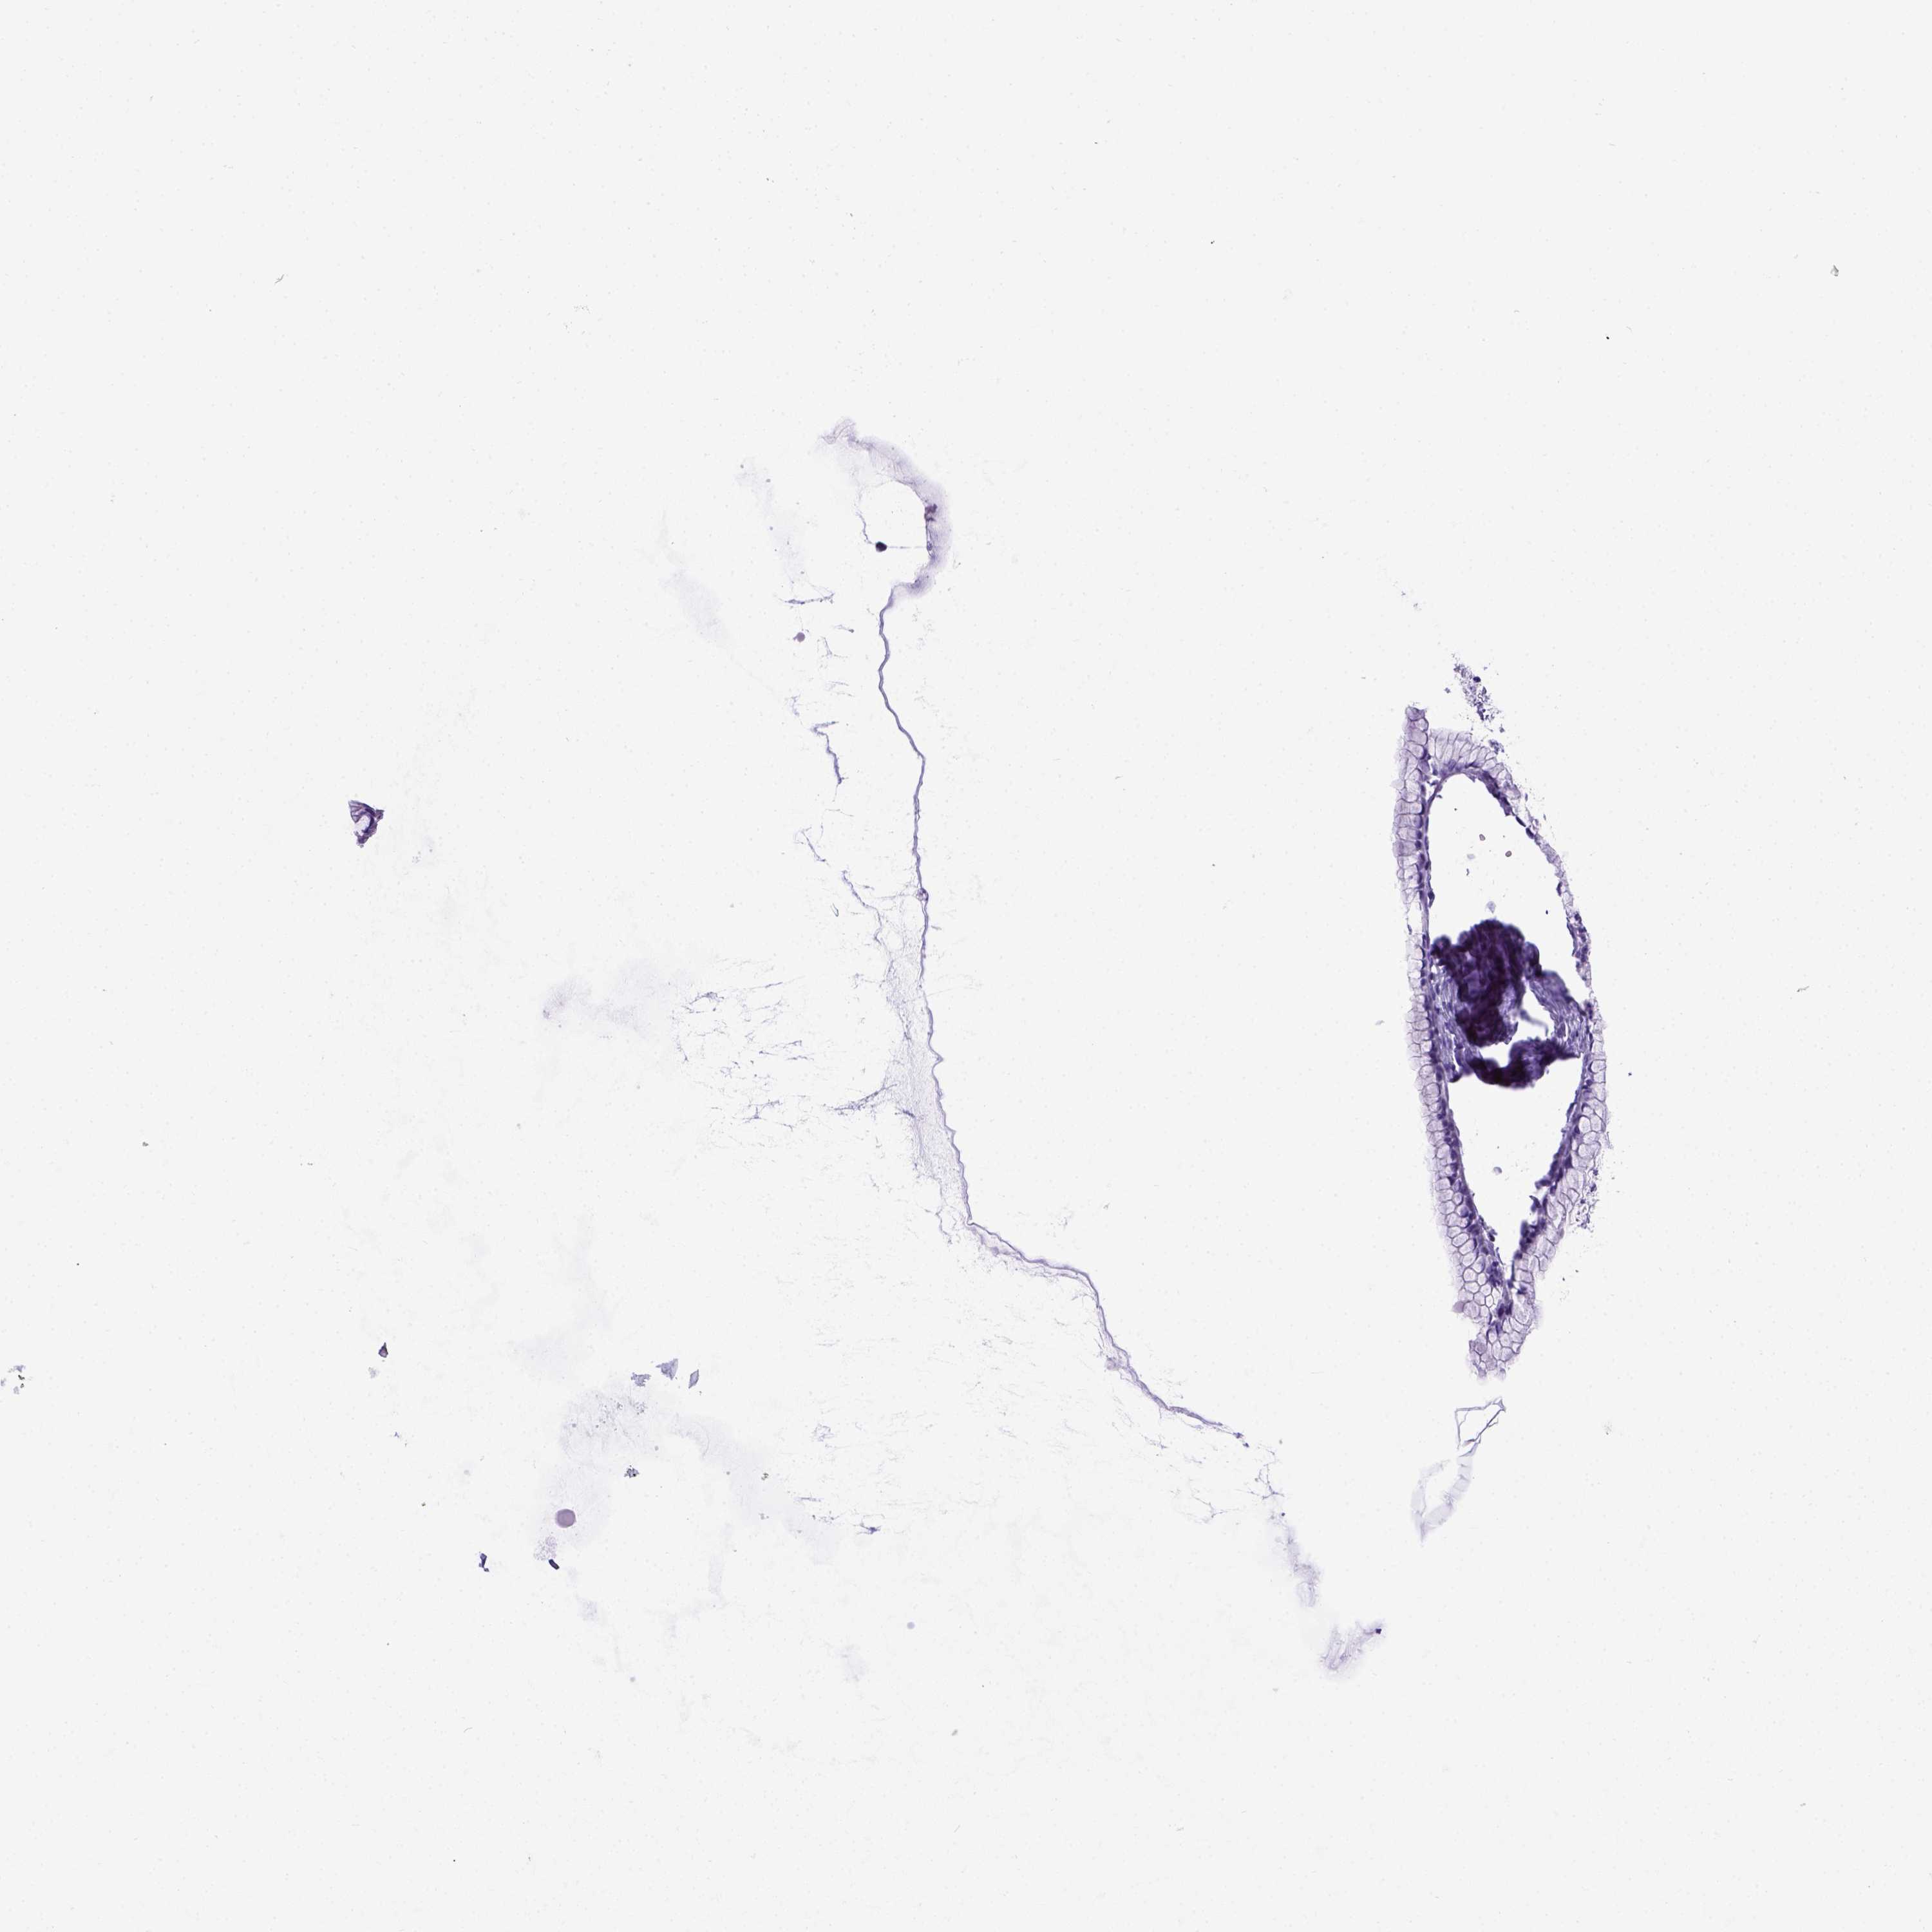

OVARIAN CANCER - Protein expressioni

A mouse-over function shows sample information and annotation data. Click on an image to view it in a full screen mode. Samples can be filtered based on level of antibody staining by selecting one or several of the following categories: high, medium, low and not detected. The assay and annotation is described here.

Note that samples used for immunohistochemistry by the Human Protein Atlas do not correspond to samples in the TCGA dataset.

Antibody stainingi

Antibody staining in the annotated cell types in the current human tissue is reported as not detected, low, medium, or high, based on conventional immunohistochemistry profiling in selected tissues. This score is based on the combination of the staining intensity and fraction of stained cells.

Each image is clickable and will lead to virtual microscopy that enables deeper exploration of all samples and also displays staining intensity scores, fraction scores and subcellular localization as well as patient and tissue information for each sample.

Antibody HPA045064

Cystadenocarcinoma, serous, NOS

Cystadenocarcinoma, mucinous, NOS

Carcinoma, endometroid